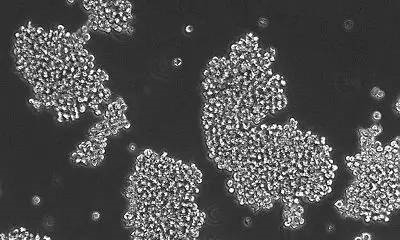

ń║”ń┐░ķ£ŹµÖ«ķćæµ¢»Õż¦ÕŁ”ńÜäńĀöń®ČĶĆģõ╗¼ķćŹńé╣ńĀöń®Čõ║åTAK228µ▓╗ń¢ŚõĖŖĶ┐░ń¢ŠńŚģńÜäµĮ£ÕŖø�ŃĆé�ŃĆé�ŃĆéŃĆé�ŃĆ鵣żÕēŹńĀöń®Čµē╣µ│©Ķ»źĶŹ»ńē®ĶāĮÕż¤ĶĘ©ĶČŖĶĪĆĶäæÕ▒ÅķÜ£�’╝ī�’╝ī�’╝ī�’╝īķÖŹõĮÄĶé┐ńśżń╗åĶā×õĖŁmTORÕŹĄńÖĮńÜäĶĪ©ĶŠŠµ░┤Õ╣│�ŃĆé�ŃĆé�ŃĆéŃĆé�ŃĆéńö▒õ║ÄõĖŖĶ┐░õĖżń▒╗ńÖīńŚćõĖŁĶé┐ńśżń╗åĶā×ńÜämTORńÜäµ┤╗µĆ¦ÕØćµ│øĶĄĘÕ╝éÕĖĖÕŹćķ½ś�’╝ī�’╝ī�’╝ī�’╝īÕøĀµŁżńĀöń®ČĶĆģõ╗¼ÕĖīµ£øTAK228ĶāĮÕż¤ÕÅ¢ÕŠŚÕźćµĢł�ŃĆé�ŃĆé�ŃĆéŃĆé�ŃĆé

Õ£©Ķ┐ÖõĖĆńĀöń®ČõĖŁ�’╝ī�’╝ī�’╝ī�’╝īRaabeÕŹÜÕŻ½ńŁēõ║║õ╗ĵéŻĶĆģõĮōÕåģń¢ÅµĢŻÕć║õ║åńÖīń╗åĶā×�’╝ī�’╝ī�’╝ī�’╝īÕ╣ČõĖöĶ«®ÕģȵğÕÅŚĶŹ»ńē®Õł║µ┐Ć�ŃĆé�ŃĆé�ŃĆéŃĆé�ŃĆéµĢłµ×£µśŠńż║�’╝ī�’╝ī�’╝ī�’╝īTAK228ĶāĮÕż¤ķÖŹõĮÄDIPGń╗åĶā×ńÜäÕó×µ«¢�’╝ī�’╝ī�’╝ī�’╝īÕ╣ČõĖöõ╝ÜķĆĀµłÉ6%ń╗åĶā×ńÜ䵫ÆÕæĮ�ŃĆé�ŃĆé�ŃĆéŃĆé�ŃĆé

ńäČĶĆī�’╝ī�’╝ī�’╝ī�’╝īÕĮōõĖĵöŠń¢ŚĶ┐×ń│╗Õ£©õĖĆĶĄĘµŚČ�’╝ī�’╝ī�’╝ī�’╝īõĮ£ĶĆģÕÅæµśÄTAK228ńÜäĶüöÕÉłµ▓╗ń¢ŚĶāĮÕż¤Õó×Õ╝║ķĆÜõŠŗÕī¢ń¢ŚµØĆõ╝żDIPGńÜäõĖĆÕĆŹńÜäµĢłµ×£�ŃĆé�ŃĆé�ŃĆéŃĆé�ŃĆéÕģ│õ║ÄAT/RTsĶĆīĶ©Ć�’╝ī�’╝ī�’╝ī�’╝īĶ»źĶŹ»ńē®ĶāĮÕż¤ĶĄĘÕł░ńøĖõ╝╝ńÜäµŖæÕłČÕó×µ«¢ńÜäµĢłµ×£�’╝ī�’╝ī�’╝ī�’╝īÕÉīµŚČĶāĮÕż¤Õż¦Õ╣ģÕó×ķ½śÕó×Ķ┐øń╗åĶā×Õćŗõ║ĪńÜäĶāĮÕŖø�ŃĆé�ŃĆé�ŃĆéŃĆé�ŃĆéõ╣ŗÕÉÄ�’╝ī�’╝ī�’╝ī�’╝īń£ŗµłÉĶĆģÕ░åTAK228õĖÄÕī¢ń¢ŚĶŹ»ńē®cisplatinĶ┐×ń│╗õĮ┐ńö©µŚČ�’╝ī�’╝ī�’╝ī�’╝īÕ░Åķ╝ĀńÜäÕŁśµ┤╗µŚČķŚ┤ĶāĮÕż¤Õ╗Čõ╝ĖÕ┐½Ķ”üõĖĆõĖ¬µ£ł�’╝ī�’╝ī�’╝ī�’╝īĶĆīÕŹĢńŗ¼õĮ┐ńö©Õī¢ń¢ŚĶŹ»ńē®µł¢TAK228µŚČ�’╝ī�’╝ī�’╝ī�’╝īÕ░Åķ╝ĀńÜäÕ»┐ÕæĮÕ╗Čõ╝ĖµŚČķŚ┤õĖŹõ╝ÜÕćīķ®Š25Õż®�ŃĆé�ŃĆé�ŃĆéŃĆé�ŃĆé